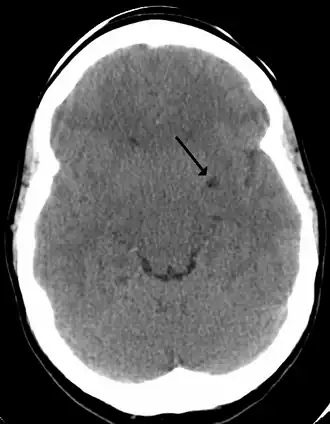

In humans, perivascular spaces surround arteries and veins can usually be seen as areas of dilatation on MRI images. While many normal brains will show a few dilated spaces, an increase in these spaces may correlate with the incidence of several neurodegenerative diseases, making the spaces a topic of research.[4]

Perivascular spaces are most commonly located in the basal ganglia and white matter of the cerebrum, and along the optic tract.[13] The ideal method used to visualize perivascular spaces is T2-weighted MRI. The MR images of other neurological disorders can be similar to those of the dilated spaces. These disorders are:[7]

Perivascular spaces are distinguished on an MRI by several key features. The spaces appear as distinct round or oval entities with a signal intensity visually equivalent to that of cerebrospinal fluid in the subarachnoid space.[7][14][15] In addition, a perivascular space has no mass effect and is located along the blood vessel around which it forms.[14]